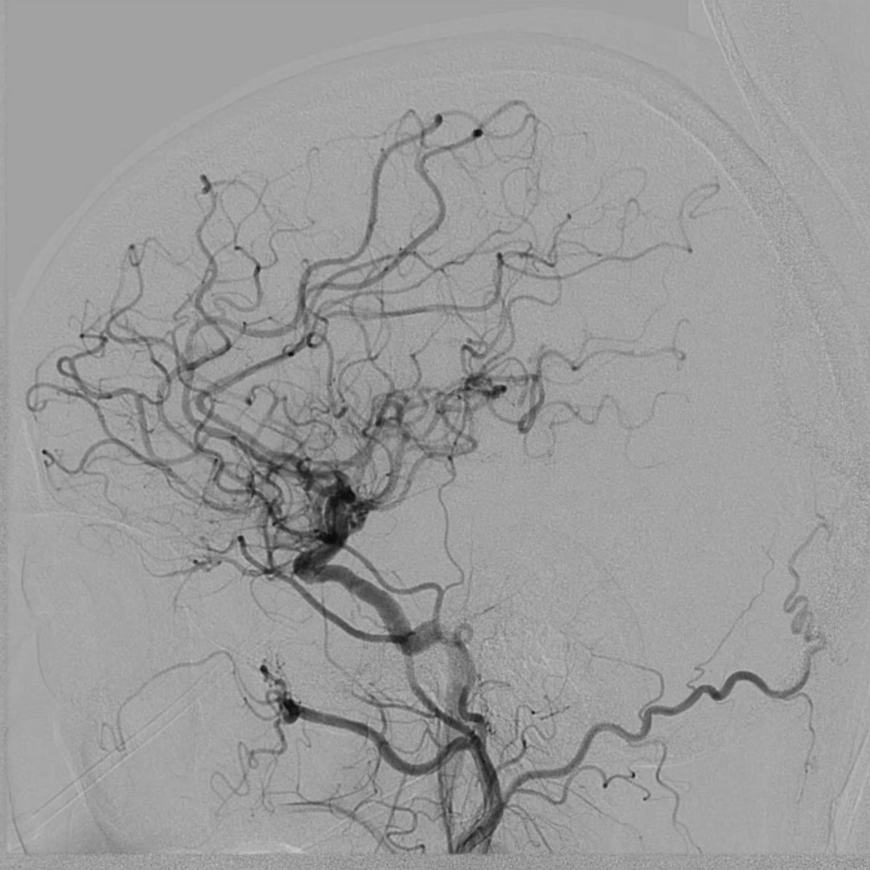

血供改善与安全性验证

造影显示:支架膨胀良好,无需后扩张;

颅内血供:左侧颈内动脉血流通畅,因右侧闭塞,左侧成为全脑主要供血通路,血供恢复满意